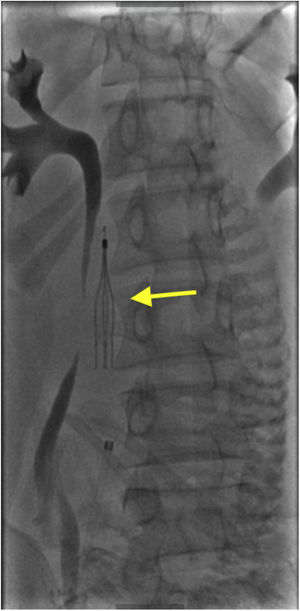

Therapeutic interventionsThe contraindication of anticoagulation and the need for immediate treatment raised the inferior vena cava filter as the most reasonable option.

ResultsAfter the placement of the filter, the delivery proceeded without incident. The plunger did not migrate and the filter was removed 29 days after delivery without complications.

ConclusionDespite our limited clinical experience in the management of these cases, we can affirm that the inferior vena cava filter represents a reasonable and safe option in cases of thrombosis of the lower limbs in women in labor.